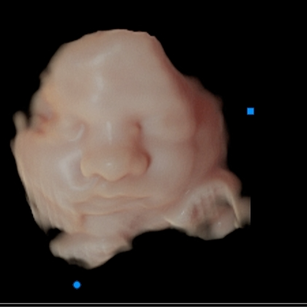

Skin: Becoming smoother as fat builds up underneath; baby is starting to look plumper and less wrinkly.

Eyes: Baby can respond to light, open and close their eyes, and even start practicing blinking.

Baby is also practicing grasping, sucking, and even hiccupping.